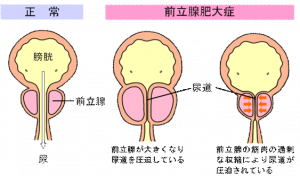

会陰部 男性-男性 感染後3~12日で会陰部や直腸粘膜に5~8mmのびらん・丘疹が発生します。 やがて潰瘍になりますが、痛みがなく数日で治ってしまうので、本人が気づかないことも多いです。 その後1~2週間で、鼠径リンパ節や大腿部リンパ節が腫れます。前立腺の病気には慢性前立腺炎、急性前立腺炎、前立腺肥大症、前立腺癌などがあります。 慢性前立腺炎 あまり知られていない病名ですが、罹患されている男性は多く、すでに治療 中でなかなか良くならず悩んでおられる方も多いと思われます。 命に関 わる病態ではありませんが、ご本人に

前立腺の病気 さくまクリニック

前立腺の病気 さくまクリニック